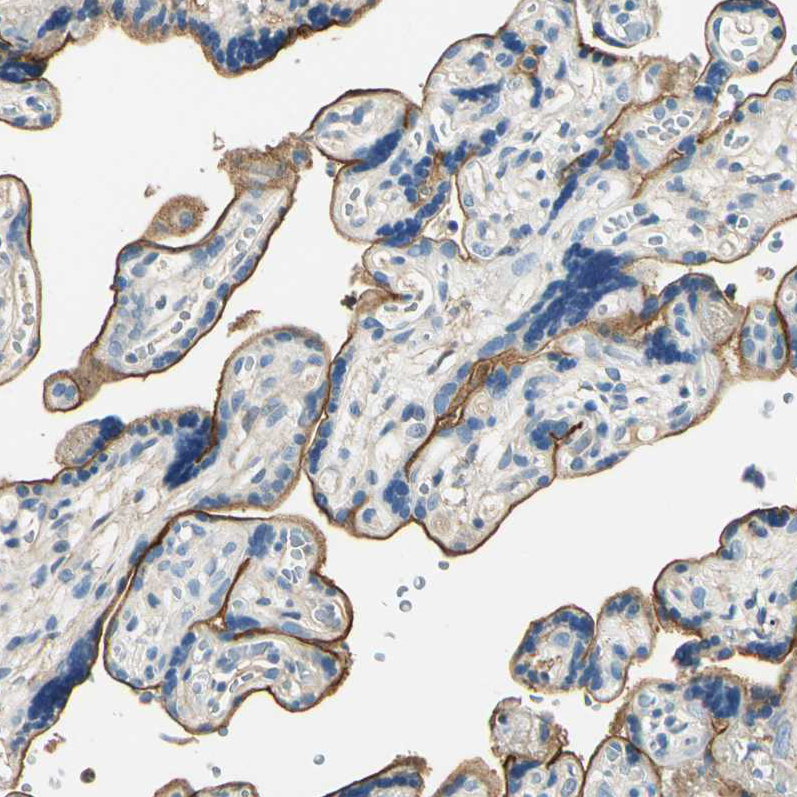

Immunohistochemical staining of human placenta shows strong membranous positivity in trophoblastic cells.